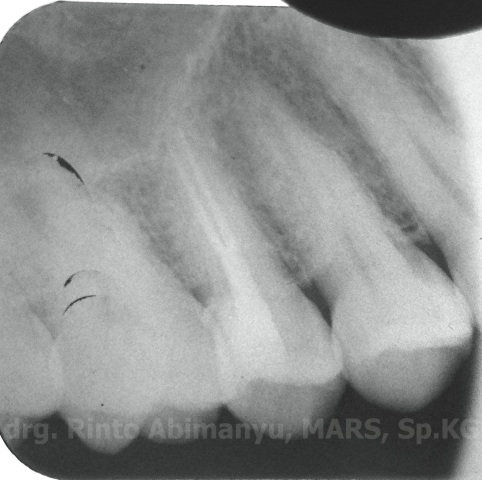

dan ini foto ronsennya…

Alhamdulillah… Tidak ada masalah selama melakukan prosedur perawatan.